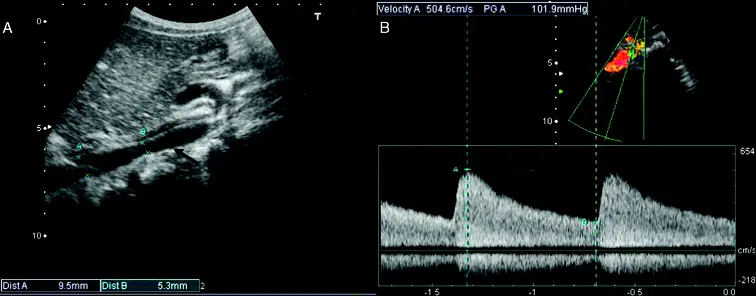

- Continuous-wave Doppler enables assessment of transaortic gradients and abdominal aortic flow.

- Coarctation of aorta for abdominal aorta U/S will be flipped (i.e. positively oriented) and less prominent (as your measuring further away from the coarctation), but similarly won’t return back to baseline